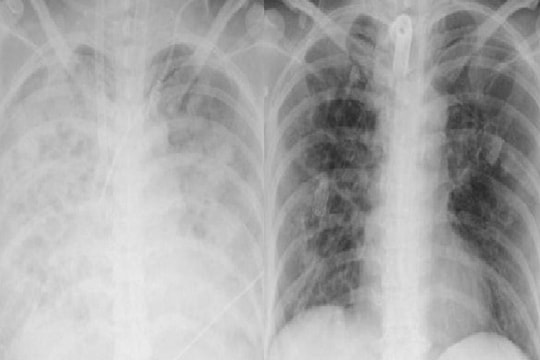

Khi đến Khoa Hồi sức tích cực, bệnh nhân thở oxy qua mask, điểm Glasgow chỉ còn 13. Chỉ sau ba giờ, hô hấp suy sụp, phải thở máy và đặt nội khí quản. Đến đêm, bệnh nhân rơi vào sốc nhiễm khuẩn, được chỉ định lọc máu và đặt ECMO để hỗ trợ tuần hoàn.

Xét nghiệm cho thấy bạch cầu tăng tới 17.000/mm³ (bình thường 4.000–10.000), Procalcitonin tăng vọt lên 260 ng/mL (gấp hơn 5.000 lần mức bình thường). Bệnh nhân bị suy gan nặng, men gan tăng cao, suy thận cấp.

“Chức năng hô hấp của bệnh nhân hiện vẫn rất kém, dù các chỉ số sinh tồn có dấu hiệu cải thiện sau ECMO. Tiên lượng vẫn dè dặt”, ThS.BS Trần Văn Quý, Trung tâm Hồi sức tích cực, cho biết.